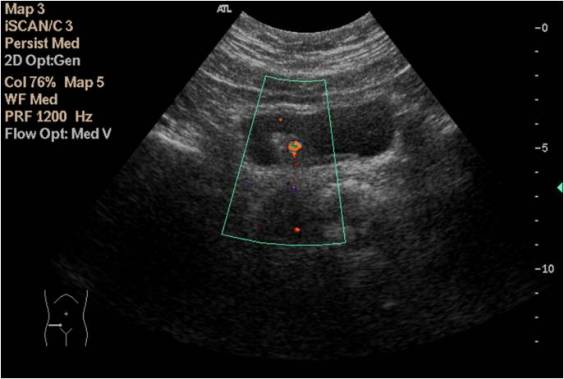

Con el doppler color podemos ver el Jet Vesical y demostrar colocando la caja de color a salida de los uréteres, el buen funcionamiento de estos ya que la eyección de orina del uréter en la vejiga se va a representar con efecto de flujo. Como se observa en estas dos imágenes siguientes: